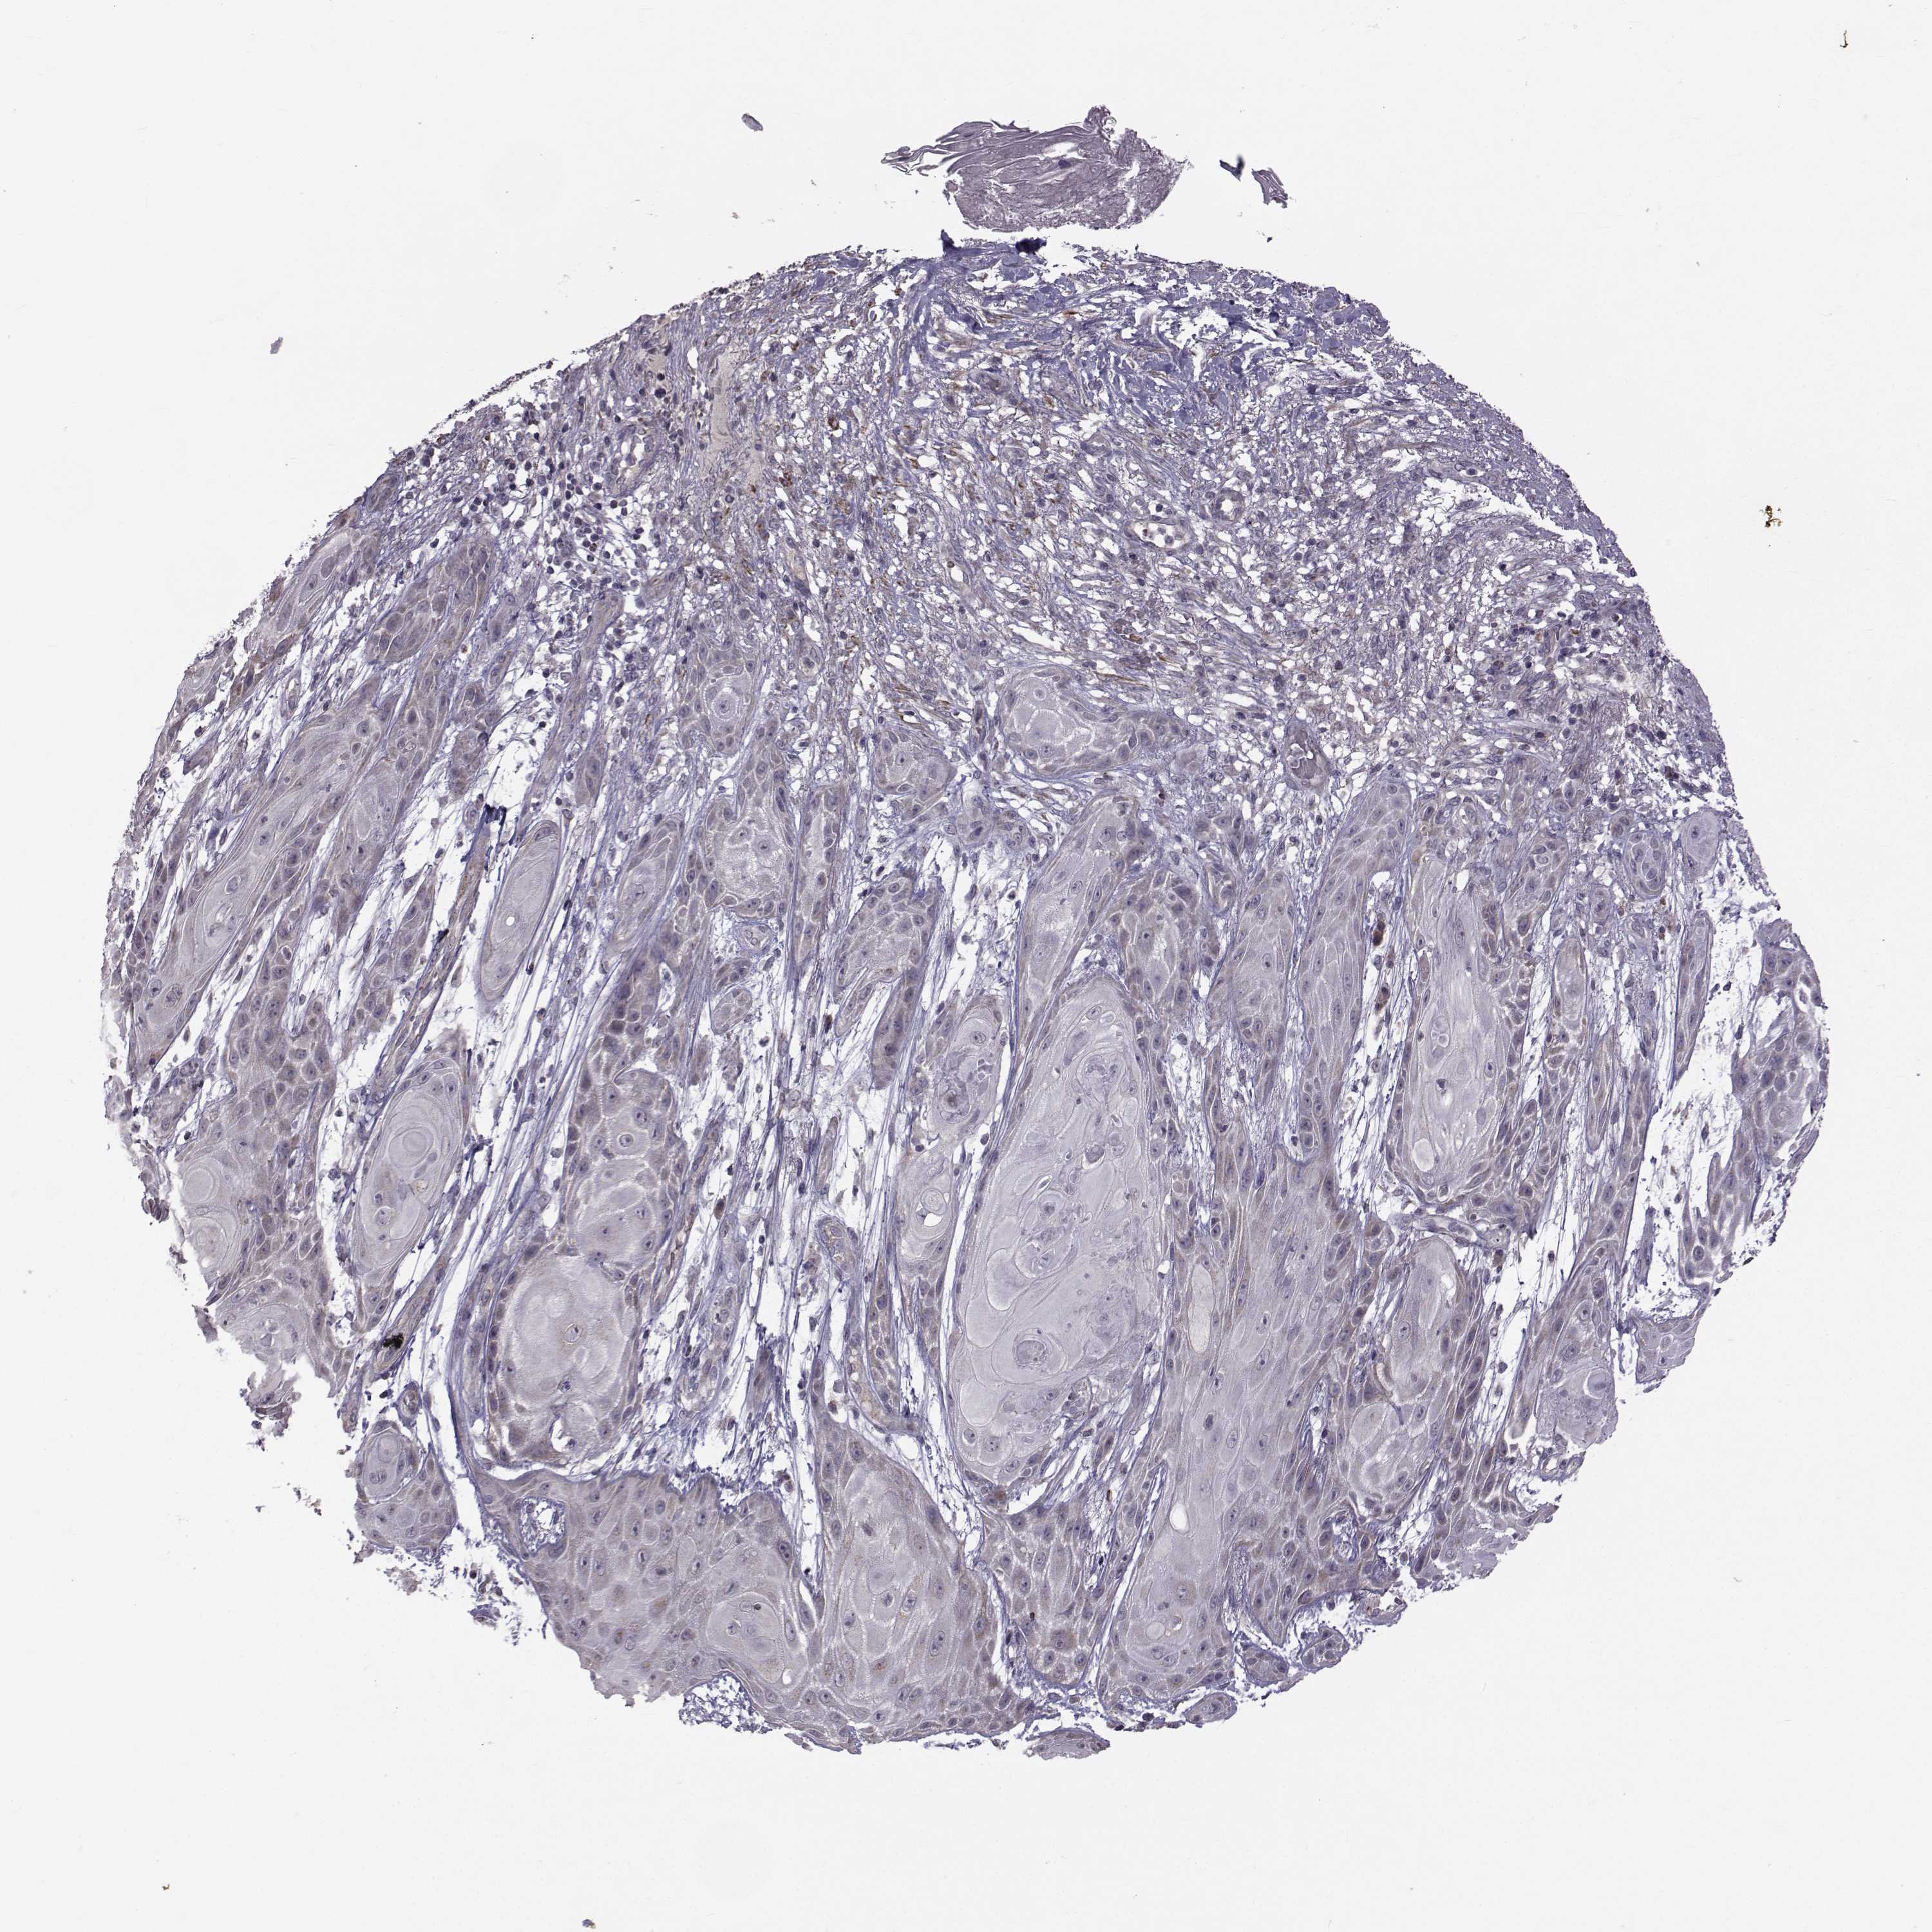

Basal cell and squamous cell cancer

SKIN CANCER - Protein expressioni

A mouse-over function shows sample information and annotation data. Click on an image to view it in a full screen mode. Samples can be filtered based on level of antibody staining by selecting one or several of the following categories: high, medium, low and not detected. The assay and annotation is described here.

Antibody stainingi

Antibody staining in the annotated cell types in the current human tissue is reported as not detected, low, medium, or high, based on conventional immunohistochemistry profiling in selected tissues. This score is based on the combination of the staining intensity and fraction of stained cells.

Each image is clickable and will lead to virtual microscopy that enables deeper exploration of all samples and also displays staining intensity scores, fraction scores and subcellular localization as well as patient and tissue information for each sample.

Antibody HPA044393

Antibody HPA053673

Antibody CAB009818

Staining

High

Medium

Low

Not detected

Intensity

Strong

Moderate

Weak

Negative

Quantity

>75%

75%-25%

<25%

None

Location

Nuclear

Cytoplasmic/membranous

Cytoplasmic/membranous,nuclear

Squamous cell carcinoma, NOS

Basal cell carcinoma